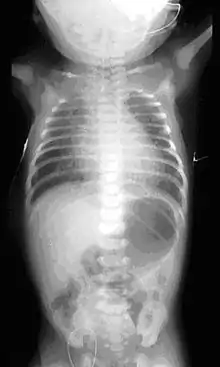

On plain X-ray, a feeding tube will not be seen pass through the esophagus and remain coiled in the upper oesophageal pouch.[3]

If any of the above signs/symptoms are noticed, a catheter is gently passed into the esophagus to check for resistance. If resistance is noted, other studies will be done to confirm the diagnosis. A catheter can be inserted and will show up as white on a regular x-ray film to demonstrate the blind pouch ending. Sometimes a small amount of barium (chalk-like liquid) is placed through the mouth to diagnose the problems.